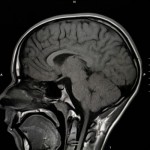

„Untersuchungen mit diesem Gerät werden von Personen mit Klaustrophobie viele besser toleriert, wichtige diagnostische Informationen können so gewonnen werden.“ Neben der speziellen Eignung für klaustrophobe und adipöse Patienten zeichnet sich das 1,5 Tesla MRT-Gerät Magnetom Espree durch eine exzellente Bildqualität insbesondere bei Untersuchungen von Gelenken, der Wirbelsäule und des Gehirns aus.

Bilder vom Gehirn, Schulter und Halswirbelsäule.